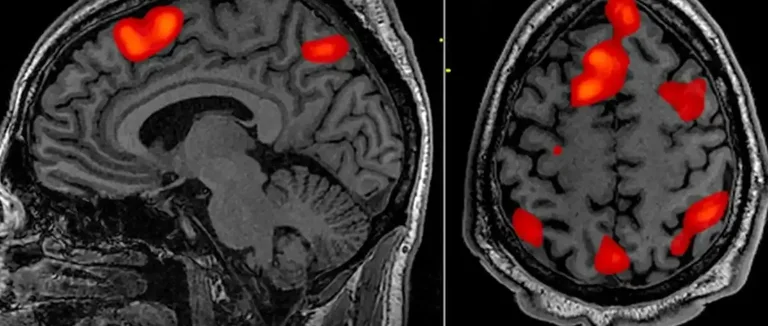

Imagerie par Résonance Magnétique (IRM)

L'Imagerie par Résonance Magnétique (IRM) est très utilisée pour diagnostiquer les kystes cérébraux. Elle donne des images détaillées du cerveau. Cela permet de voir la taille, la localisation et les caractéristiques du kyste.

L'IRM est sûre car elle ne nécessite pas d'exposition aux rayons X. Cela la rend idéale pour les patients qui ont besoin d'examinations répétées.

Tomodensitométrie (TDM) et Autres Techniques

La Tomodensitométrie (TDM), ou scanner CT, est aussi une méthode importante. Elle utilise des rayons X pour créer des images du cerveau. Cela aide à identifier les kystes et à voir leur impact sur le cerveau.